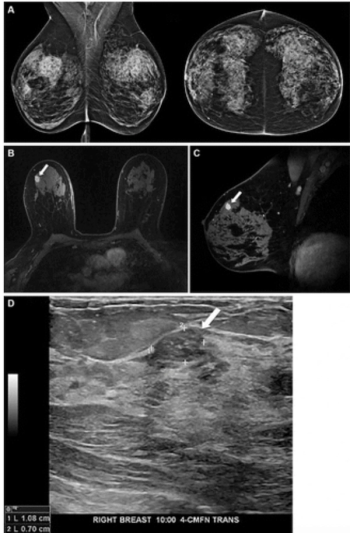

New research suggests the capability of a mammography-based deep learning model to identify women at high risk of breast cancer led to more than triple the cancer detection rate on breast MRI in comparison to traditional risk assessment tools.